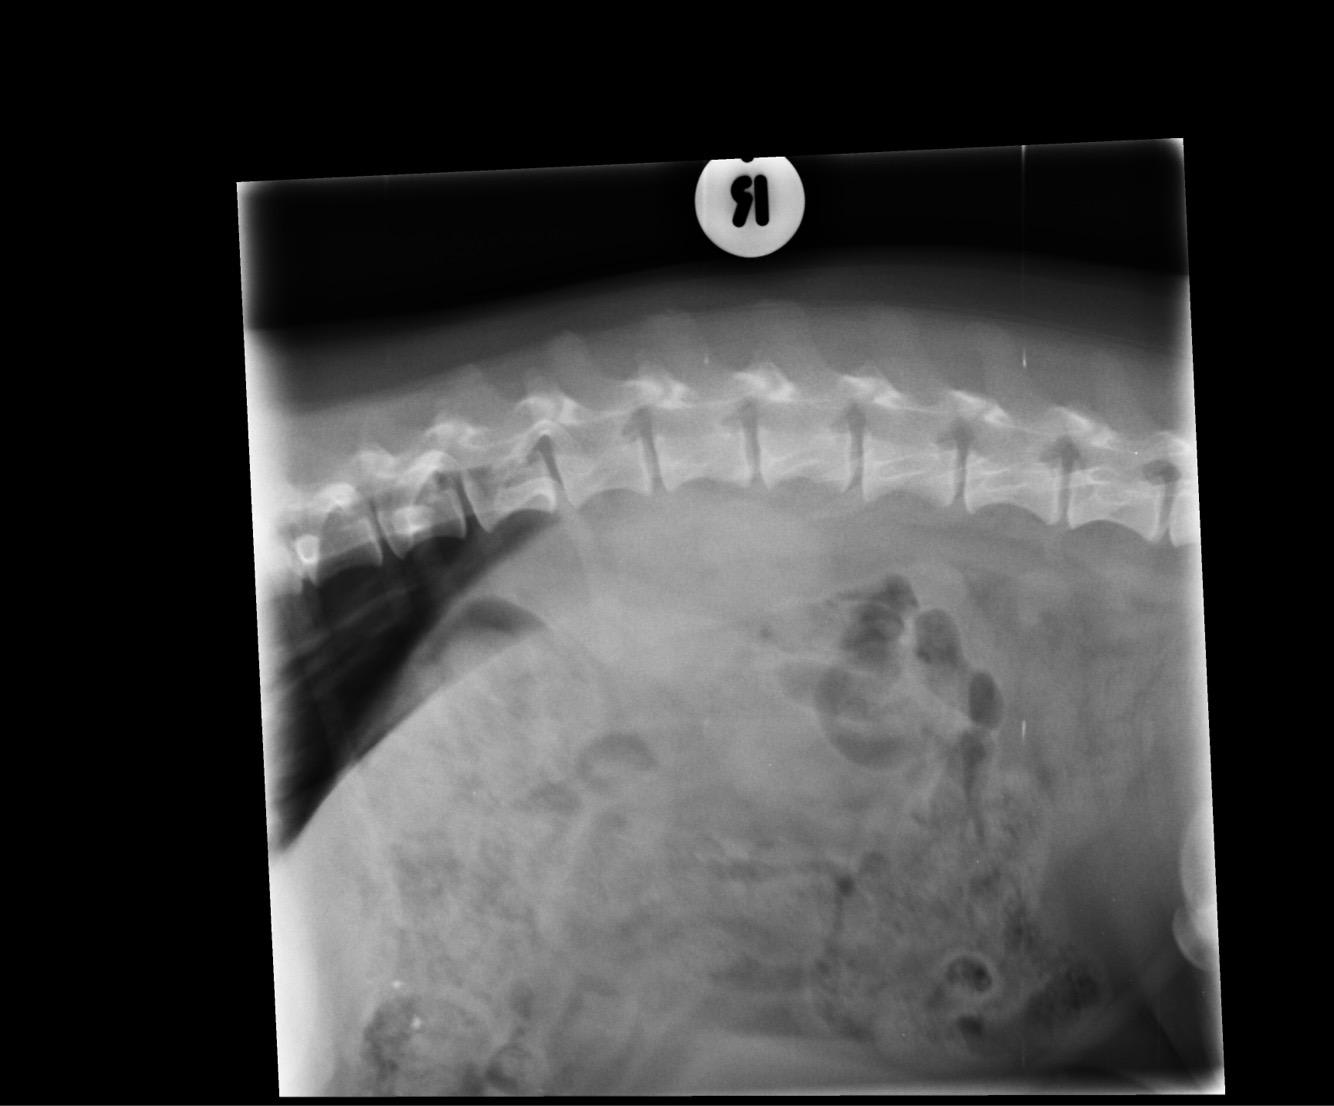

I have recently lost my dog to cancer. He had a bump on his torso on the left hand side. They did X-rays, blood tests and recommended a biopsy. We decided to opt for the biopsy, she described the bump as a bloody cavity that squirted and the results came back as attached. The bump was gone, we were instructed to give him metacam and watch if it returned. It returned 5 weeks later and was diagnosed sarcoma, but it was too late to remove. I want to know if a scan or operation could have saved him?

Hi, thanks for using Petco Pet Education Center, formerly Petcoach! Poor Rolo! From the biopsy report Rolo had hemandiosarcoma which is a very aggressive cancer of the blood vessels. We most commonly see if on the liver, spleen or right atrium of the heart. By the time it has grown it has microscopically spread else where. It is a very aggressive cancer and even with chemotherapy/radiation and surgery most dogs get more or less than 6 months after diagnosis. I do not think anything else would have cured Rolo. I am very sorry for your loss.